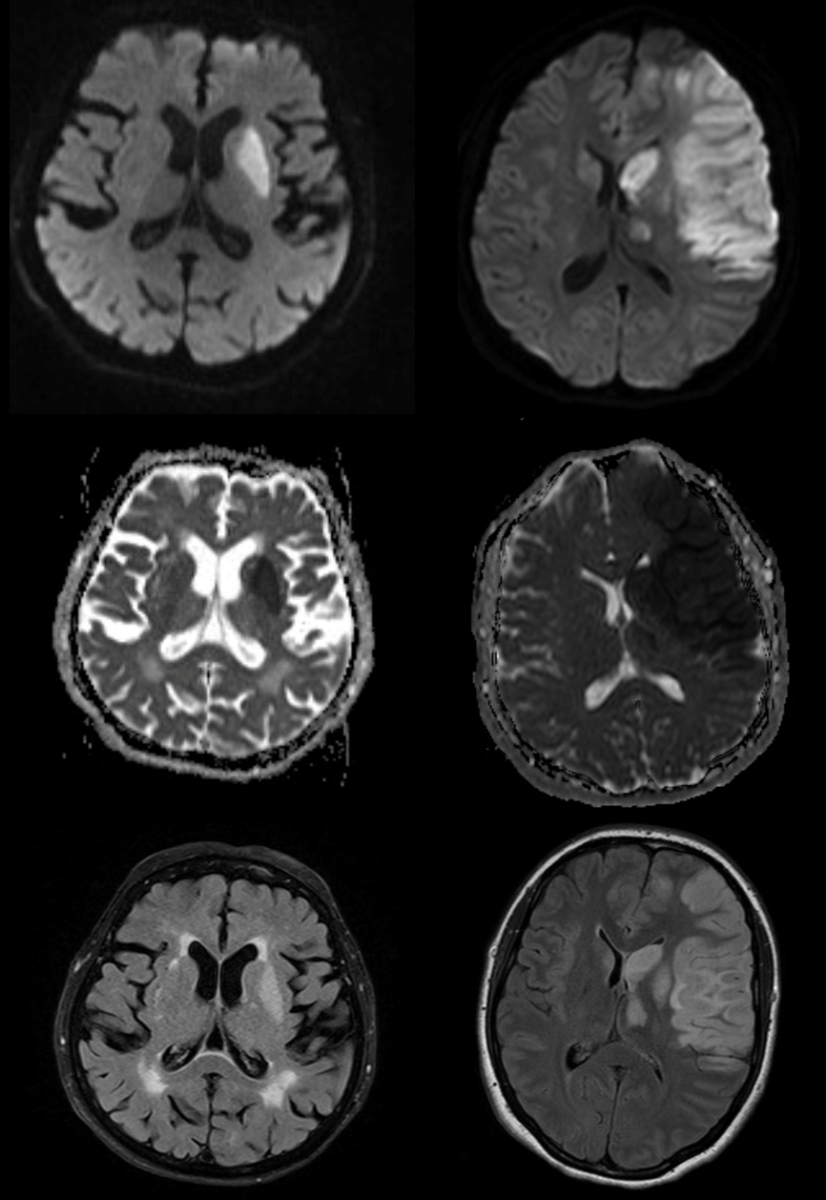

Jako specjalista neurolog zajmuję się diagnostyką i leczeniem przede wszystkim stwardnienia rozsianego oraz innych chorób demielinizacyjnych, a także migreny i innych bólów głowy.

• udar mózgu,

• guz mózgu.